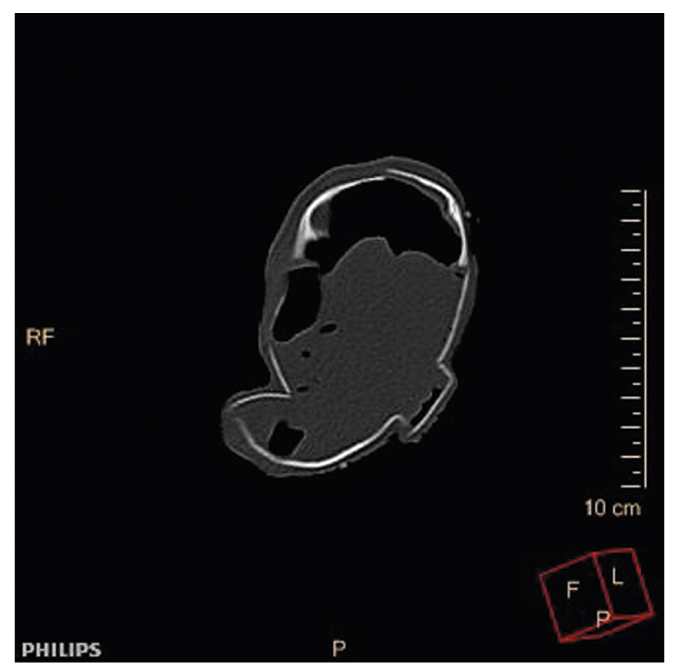

При КТ основными находками были костные повреждения: множественные повреждения и переломы костей черепа (рис. 8, 9) — лобной кости, чешуи слева, глазничной и носовой части лобной кости слева, обеих теменных костей, затылочной кости (базилярной, латеральной частей и чешуи) со смещением, захождением и деформацией костных отломков, височных костей, тела и больших крыльев основной кости; расхождение швов мозгового и лицевого черепа с деформацией черепной коробки в виде уплощения с боков; перелом скулоорбитального комплекса справа; позвоночного столба (латеральное смещение С1-позвонка вправо, С7-позвонка влево); полная сепарация позвоночного столба с большим диастазом на уровне середины тела Th11-позвонка, с переломом тела позвонка; множественные переломы большинства ребер; полная сепарация всех ребер слева на уровне реберно-позвоночных сочленений, с диастазом; деформация грудинного конца ключицы справа; переломы крыла подвздошной кости справа, седалищной кости справа; неполный перелом средней трети диафиза правой бедренной кости, средней трети диафиза правой большеберцовой кости. Вещество головного мозга было в состоянии декомпозиции (см. рис. 8), представлено мягкотканным субстратом с наличием газа и плотных включений; воздухоносные пространства пирамид височных костей выполнены мягкотканным субстратом. Левое глазное яблоко деформировано, неправильной формы. Ушные раковины и наружный нос правильно сформированы, деформированы. Грудная клетка деформирована, гемитораксы асимметричны. Средостение представлено в виде отдельных мягкотканных элементов с наличием плотных включений. Сердце в размерах не увеличено, располагается вне грудной полости. Легочная ткань: легкие располагаются вне грудной полости, повышенной плотности (тотально уплотнены), не расправлены (рис. 10). В структуре легочной ткани прослеживаются элементы газа, отдельные — в виде трубчатых структур — вероятно, отображение бронхов. В толще легочной ткани и вокруг видны структуры высокой плотности — вероятно, инородные тела в сочетании с костными фрагментами. Визуализируются трахея и проксимальные отделы правого и левого главных бронхов; дистальнее просвет бронхов обрывается. Нарушение целостности брюшной стенки с полной эвентрацией органов. Полые и паренхиматозные органы представлены мягкотканными структурами без органной дифференциации, смешанными с инородными телами, чередующимися с множественными пузырьками газа. Газ определялся в мягких тканях, в том числе мошонке, грудной клетке, малом тазу, полости черепа, позвоночном канале.

Рис. 9. КТ, 3D-реконструкция: полная сепарация позвоночного столба на уровне середины тела Th11-позвонка; множественные переломы большинства ребер.

Fig. 9. Computed tomography, 3D reconstruction: complete separation of the spinal column at the midpoint of the Th11 vertebral body; multiple fractures of most of the ribs.